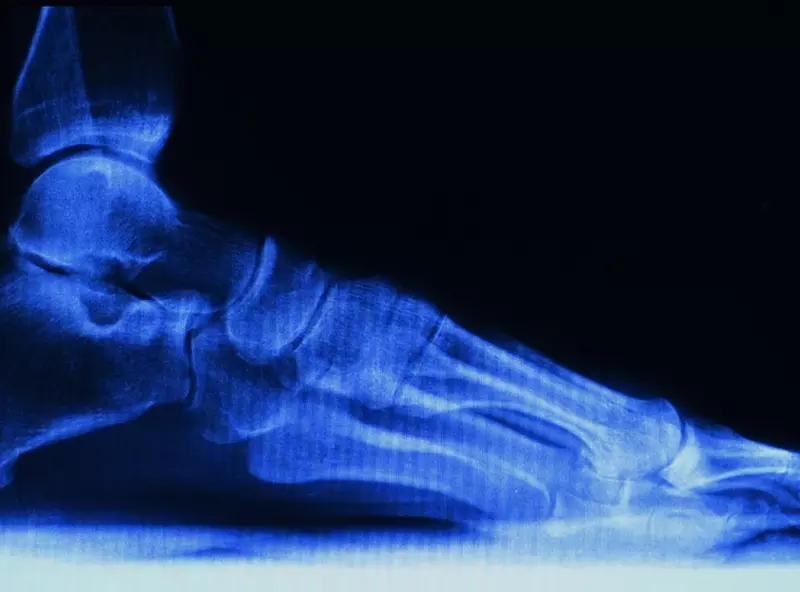

Konstrukcja stopy stanowi genialny przykład biotensegracji w przyrodzie. Dzięki specjalnemu ukształtowaniu kości, powierzchni stawowych i aparatu więzadłowego łączy lekkość konstrukcji z jej niesamowitą wytrzymałością i walorami ruchowymi. Jako najbardziej obciążana część ludzkiego szkieletu stopa potrafi zaadaptować się do nierówności terenu i wytrzymać gwałtowne zwyżki tego obciążenia (skoki, upadki, odbicia).

Od części tylnej (stępu), zbudowanej z masywnych kości spełniających funkcję podporową, do coraz drobniejszych kości śródstopia i przodostopia z licznymi stawami wzmocnionymi skomplikowanym aparatem więzadłowym stopa adaptuje się do funkcji inteligentnego resoru i sprężyny. Amortyzuje, dynamicznie rozprasza energię sił grawitacji, ale również potrafi ją zmagazynować przez napięcie układu więzadłowego i oddawać w czasie chodu, biegu czy też skoków. Stopa jest też nadzwyczaj czujnym narządem czucia głębokiego sprzężonym z układem koordynacji ruchu i równowagi.

Staw skokowy tradycyjnie omawia się, analizując dwa jego piętra. Piętro górne, utworzone przez staw skokowy górny (skokowo-goleniowy) łączący kości piszczelową i strzałkową z kością skokową, należy do stawów zawiasowych złożonych. Piętro dolne (staw skokowy dolny) zawiera dwa przedziały: przedni utworzony przez staw skokowo-piętowo- łódkowy oraz przedział tylny utworzony przez staw skokowo-piętowy o powierzchniach stawowych zaklasyfikowanych jako stawy jednoosiowe złożone. Staw skokowo-goleniowy utworzony przez powierzchnie stawowe dalszej nasady kości piszczelowej oraz strzałkowej tworzy tzw. widełki stawu skokowego wchodzące w relację z powierzchnią stawową bloczka kości skokowej [1].